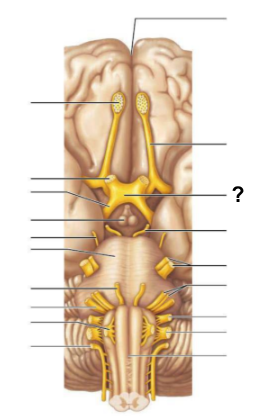

What structure, labeled “?”, is the starting point of cerebrospinal fluid circulation in the brain?

Lateral ventricle

From the lateral ventricles, CSF flows through which structure, labeled “?”, to reach the third ventricle?

Interventricular foramen

After the third ventricle, CSF flows through which narrow passage, labeled “?”, to reach the fourth ventricle?

Cerebral aqueduct

What are the two apertures, labeled “?”, through which CSF exits the fourth ventricle to enter the subarachnoid space?

The median aperture and the lateral apertures

Which structure surrounds the brain and spinal cord, allowing CSF to circulate?

Subarachnoid space

Through which structure, labeled “?”, is CSF absorbed into the venous blood?

Arachnoid villi

Into which venous system does CSF drain after passing through the arachnoid villi?

Dural venous sinuses

What is the function of the central canal in CSF circulation?